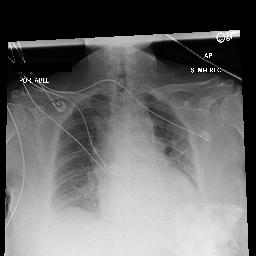

Refer to caption

Figure 1: A chest X-ray and its associated report written by a radiologist.

Diagnostic radiology is the medical field of creating and evaluating radiological images (radiographs) of patients for diagnostics. Radiologists are trained to simultaneously identify various radiological findings (e.g., diseases), according to the details of the radiograph and the patient’s clinical history, then summarize these findings and their overall impression in reports for clinical communication (Kahn Jr et al., 2009; Schwartz et al., 2011). A report typically consists of sections such as history, examination reason, findings, and impressions. As shown in Figure 1, the findings section contains a sequence of positive, negative, or uncertain mentions of either disease observations or instruments including their detailed location and severity. The impression section, by contrast, summarizes diagnoses considering all report sections above and previous studies on the patient.